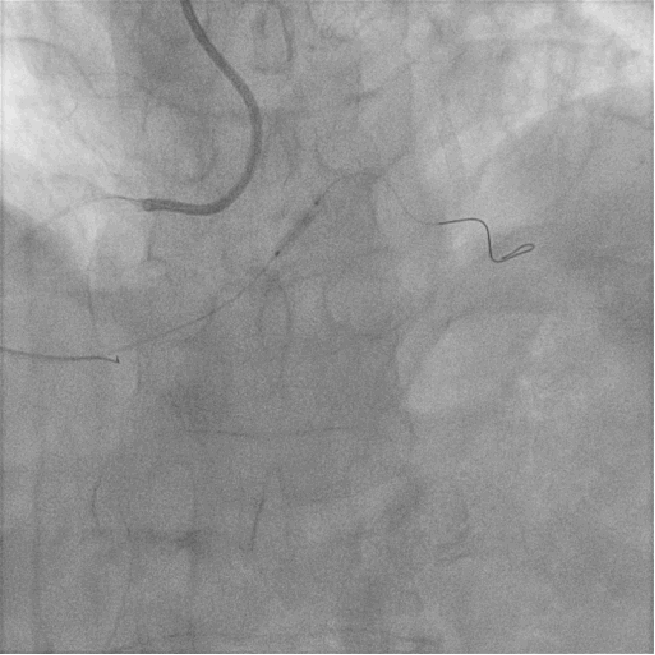

左图:LM未见狭窄及阻塞病变;

右图:LCX未见狭窄及阻塞病变;

左图:LAD近段可见斑块,中段原支架通畅,未见狭窄及阻塞病变;

右图:RCA开口狭窄约50%,近段中段弥漫性斑块,远段后侧支第二转折处局限性狭窄90%;